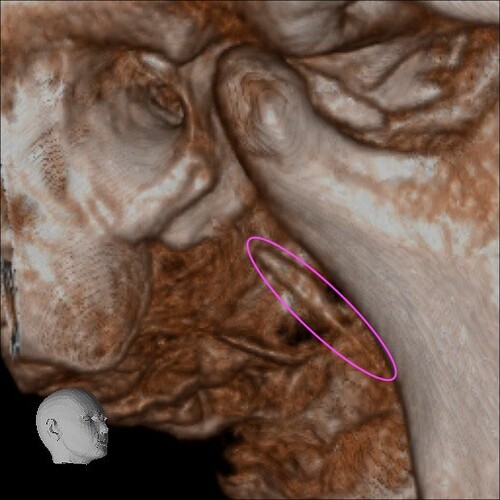

Below are some screenshots from my Cone Beam CT scan and the report linking possible ES. I have more Regular CT scans I could possibly share and/or if you would like me to get possible better angles from the Cone Beam CT scan let me know. But as of right now I’m at a loss as what to do going forward. I do have an MRI with and without contrast of the Cervical Spine Scheduled, but that’s due to the doctor’s (the doctor that dismissed it as ES and one doctor that wants to follow up and learn more on it) wanting it.

- Now onto this year, I finally got better back to full health in late November early December 2024 and sadly started to get another sinus infect in January and still no answers to why. I just happen to be watching YouTube when a Dentist had said that your teeth could be linked to sinus issues causing sinus infections and normally the only way to tell if this is the case is to get a Cone Beam CT scan. I then thought this could be another lead to find out why I keep getting sick as I did when I was 10 have my first top premolar on my left side removed against what I wanted as they said my teeth were too crowded and it needed to be removed so I could have braces (which that dentist didn’t even do my braces anyway). But I thought when he removed it if a small piece of the root was still in there as he just broke out the tooth without removing it via surgical means that that could cause an abscess in my Left Maxillary Sinus where infections always start. So, finally I was able to find a place that would give me a Cone Beam CT scan back in February of this year all while I was just starting to get sick from my infection. Anyway, I finally got the report in March and found out oddly my Left side is mostly normal other than mucus polyps, but I have a few other issues (I have attached the report below). This report is where I first found out about Eagle Syndrome as it states I might have Calcified Ligaments and further testing is needed to confirm. It was only after this report and looking up what Eagle Syndrome was that I can say I have almost every symptom that has ever been reported. Sadly, I couldn’t find anyone in my State at the time that work with Eagle Syndrome and when I did was about a week before I found this site and the doctor I did see seemed to dismiss me as another hypochondriac and you can’t have it as you don’t have Vertigo type Dizziness, my styloid are normal length and I don’t have neck pain equivalent to having to be in a neck brace. Not only this she only looked at my CT scan from a week earlier that I had got in Emergency. The Emergency visit was due to the fact at 8PM that night I had pain in my Right Mastoid Bone, and I was starting to get an earache. I went to lay down and took pain meds and an ice pack in hopes to reduce the pain and swelling. I couldn’t sleep due to the pain and came upfront about 10PM. 10:21PM I couldn’t take it anymore and started to stretch my neck and I felt a huge snap and heard a load pop, all the pain just felt like it disappeared. One minute later, I had a massive pain that spread just like when you get an IV that stings, but it felt like someone was trying to murder me and stabbed a knife into the right side of my skull. I was in so much pain that I was hunched over, and we had to have an ambulance called. I thought I was having an aneurism and my mother thought I was having a Stroke (very rare ES Symptom). When the ambulance arrived, they took my vitals, and my blood pressure was 148/110 with a pulse in the high 90’s low 100’s. Luckily the pain had subsided enough that we were able to go to emergency without the ambulance ride, but while I was in emergency the pain had spread to my left side of my head and now felt like someone had taken a clothes iron and stuck it on my head. Any breeze moving my hair was pure agony and I couldn’t lay my head on a pillow without that burning pain. According to emergency though I must have just had a Mastoid Process infection and it burst. Luckily the pain went away by the time I went to the Doctor for ES, but like I said before they were of no help.